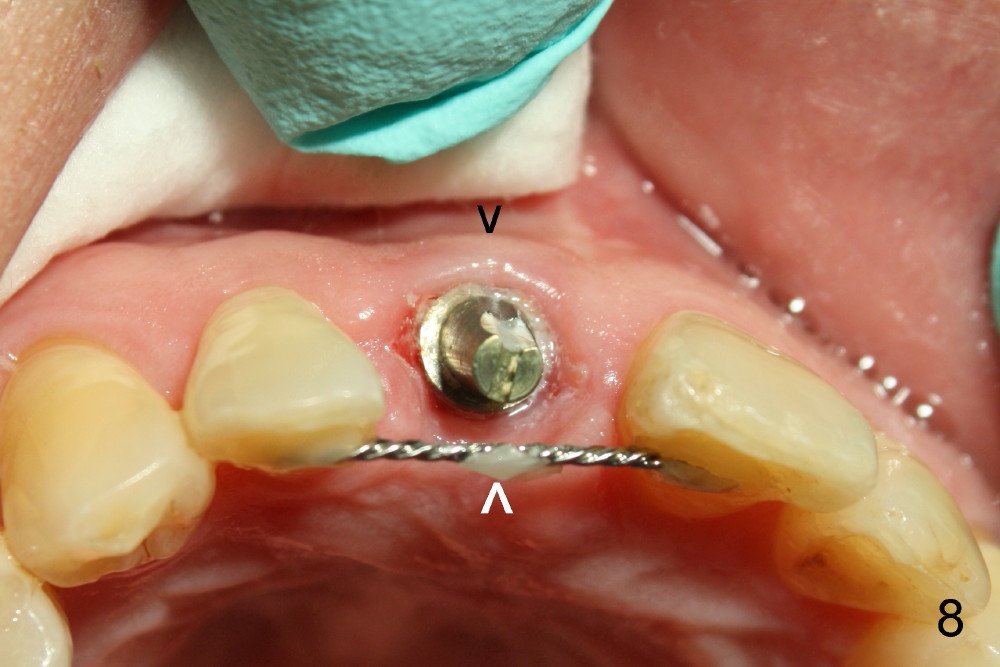

The provisional is dislodged 3.5 months postop; there is no labial atrophy (Fig.8 black arrowhead). The permanent crown (Fig.9 C) is harmonious with the papillae (*). When the try in crown is removed, the gingival tissue looks healthy (Fig.10 *).